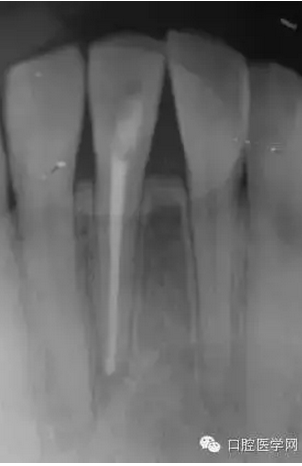

(圖 3) 根管充填

根管充填1個(gè)月后復(fù)診檢查過(guò)之后,一年后再次復(fù)診。如(圖5),可見(jiàn)大范圍破壞根尖周病變大部分基本治愈。

(圖 4) 根管充填1個(gè)月后

(圖 5) 根管充填約1年后